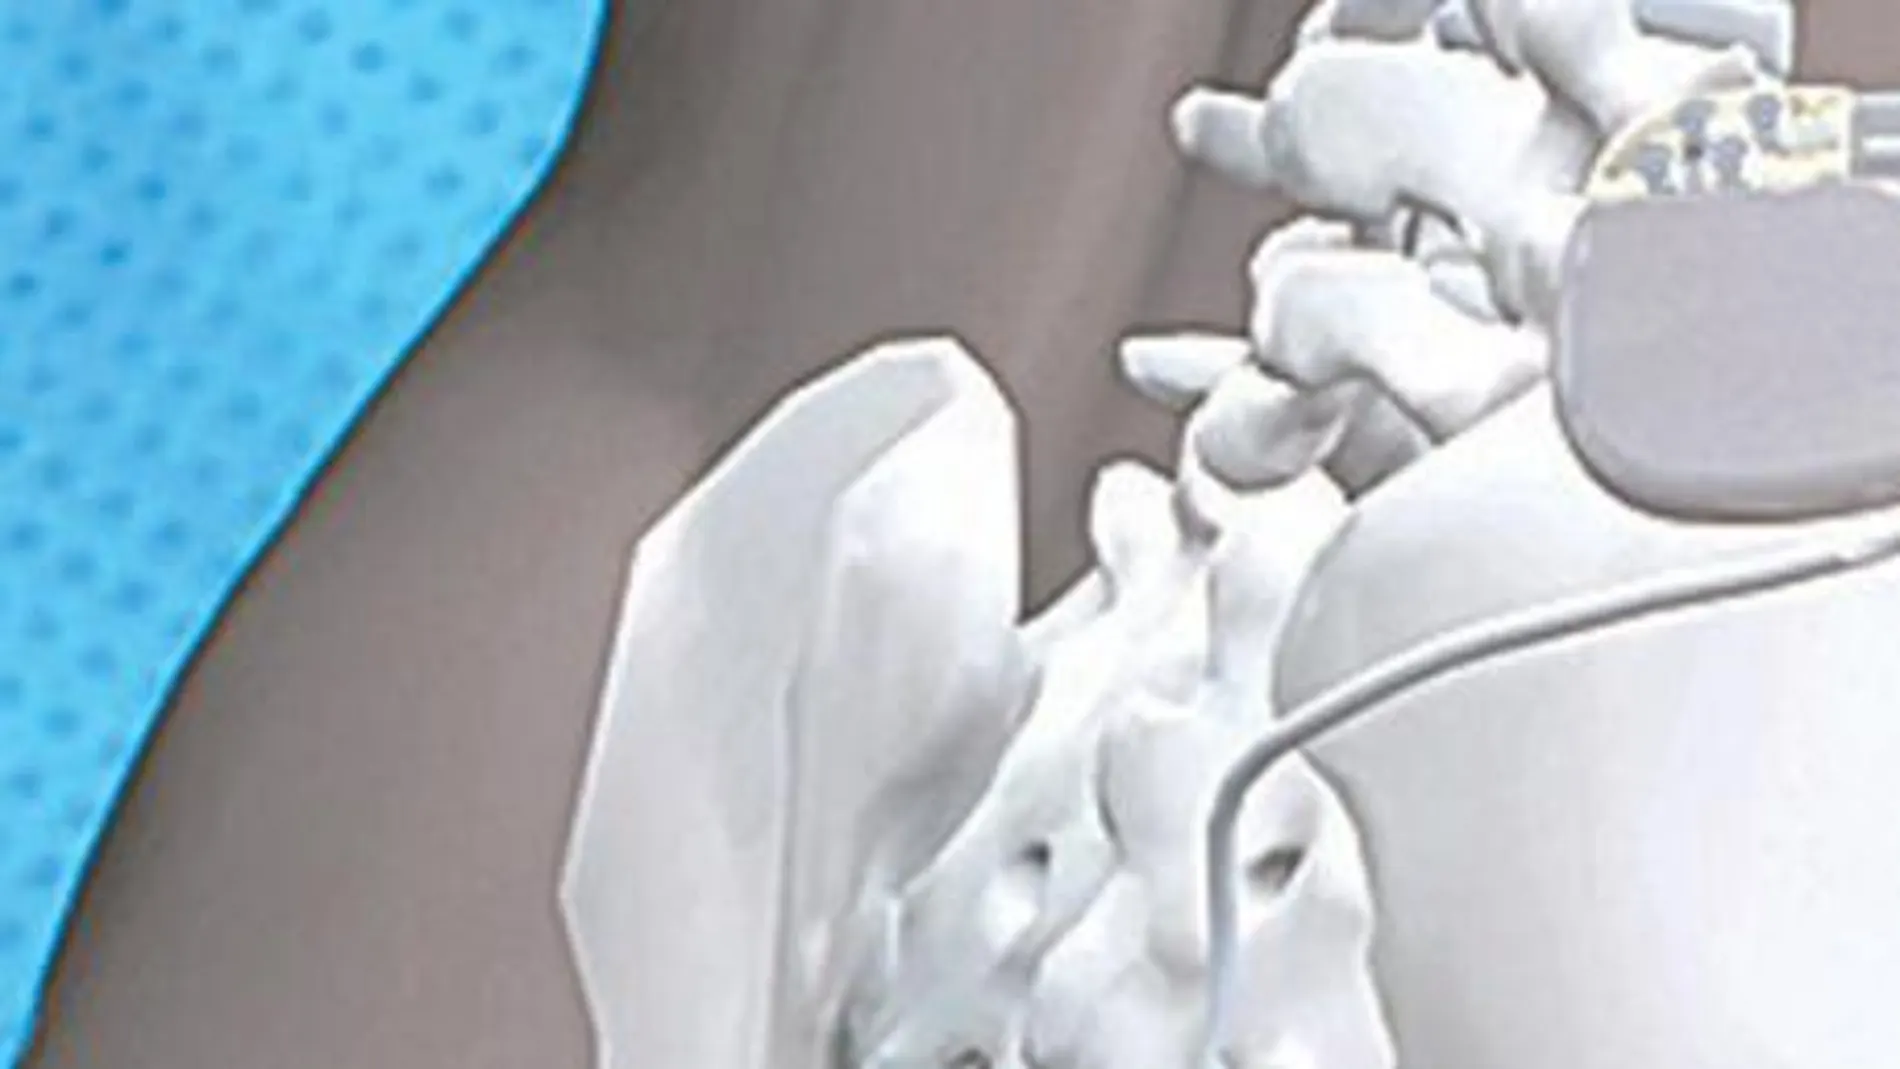

La terapia de neuromodulación de las raíces sacras es coste-efectiva para el tratamiento de la incontinencia fecal severa dentro del sistema sanitario español. Así lo recogen las conclusiones de un estudio publicado en el «British Journal of Surgery». Además, casi el 50 por ciento de los pacientes implicados en el trabajo científico experimentaron una remisión completa de los episodios de incontinencia fecal gracias a esta técnica, con lo que el uso de la terapia se asoció con una significativa mejora en su calidad de vida. El trabajo, que se ha llevado a cabo por el Hospital Mutua de Terrassa (Barcelona), lo ha dirigido Arantxa Muñoz-Duyos y Albert Navarro de la Unidad de Coloproctología del Departamento de Cirugía General de dicho centro. La eficacia y la mejora en la calidad de vida conseguida resulta eficiente para el sistema sanitario español queda demostrada si se compara el coste adicional con el valor que se obtiene de la eficacia de la terapia, y se considera el valor adecuado de disponibilidad a pagar en España. En este sentido, Muñoz-Duyos destaca que «las autoridades sanitarias deberían potenciar el tratamiento de pacientes con trastornos funcionales como la incontinencia fecal, porque implican un importante gasto sociosanitario. Se debería impulsar la creación de unidades especializadas multidisciplinares y autorizar más tratamientos, sobre todo los que han demostrado ser eficaces y eficientes».